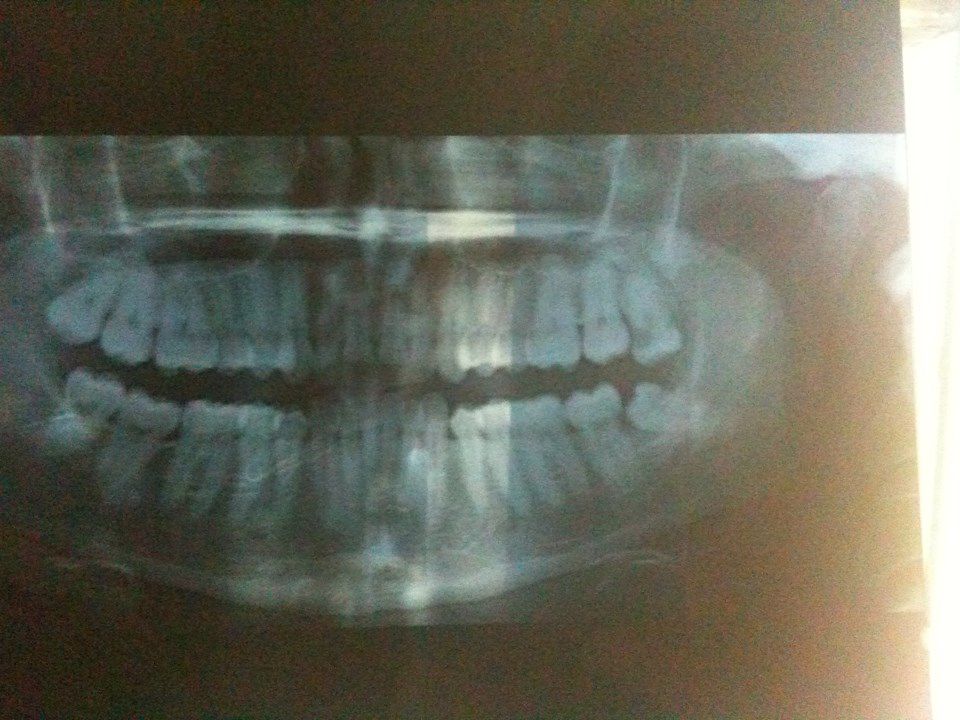

| Dire merci | ah bon ??? nan ??? purée j'espère que j'aurai pas un scan à faire ![]() voici le plus beau sourire colgate : ![]() La dent de sagesse à l'horizontale en bas à droite et celle du dessus cariée bien comme il faut Maintenant reste à appeler le chir ... je flippe ![]() mais pas le choix ! |

Par imnohuman : le 26/11/13 à 19:31:20

Déconnecté | Oooh quelle belle bouche pleine de dents Ma radio je l'avais faite directement chez le stomato ! |